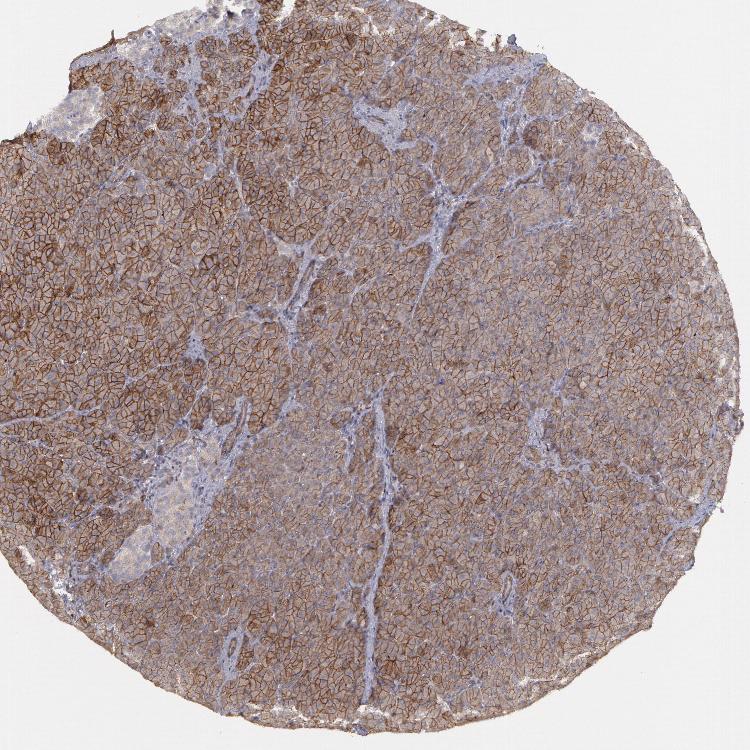

PANCREAS - Antibody stainingi

Antibody staining in the annotated cell types in the current human tissue is reported as not detected, low, medium, or high, based on conventional immunohistochemistry profiling in selected tissues. This score is based on the combination of the staining intensity and fraction of stained cells.

Each image is clickable and will lead to virtual microscopy that enables deeper exploration of all samples and also displays staining intensity scores, fraction scores and subcellular localization as well as patient and tissue information for each sample.

Antibody HPA001383Antibody CAB000043Antibody CAB020416Antibody CAB062555

Exocrine glandular cells MediumNot detectedNot detectedNot detected

Pancreatic endocrine cells LowNot detectedNot detectedNot detected